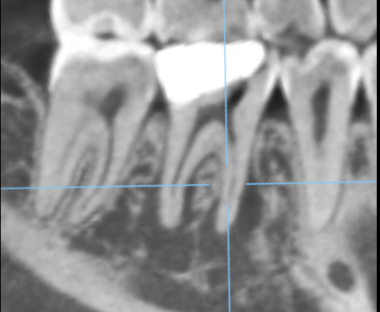

右下奥歯に瘻孔を認め、歯肉の腫脹を認めた。レントゲンで周囲骨が高度に吸収していた。

治療前